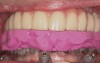

Figure 16  Laboratory-processed provisional restoration fabricated prior to surgery.

Figure 16

Figure 17  Provisional restoration placed at time of surgery.

Figure 17